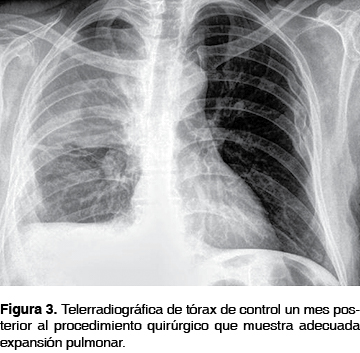

El estudio microbiológico del líquido pleural resultó negativo para Mycobacterium tuberculosis por técnica de PCR y cultivo positivo para Staphylococcus aureus meticilino sensible, por lo que no requirió ajuste de tratamiento manteniéndose por 21 días. Durante este período el paciente estuvo afebril en adecuado control metabólico con esquema de insulina basal. Dos días posteriores a la cirugía se retiró la sonda endopleural anterior, y siete días después se retiró la sonda posterior y del orificio fistuloso. El paciente egresó a los ocho días del evento quirúrgico con control radiográfico al mes que mostró reexpansión pulmonar (figura 3). Clínicamente con orificio fistuloso aún dehiscente de aproximadamente 4 mm con drenaje de escaso material purulento sin fuga aérea. Se continuó vigilancia por la consulta externa y se logró el cierre del orificio fistuloso en un mes sin complicaciones.